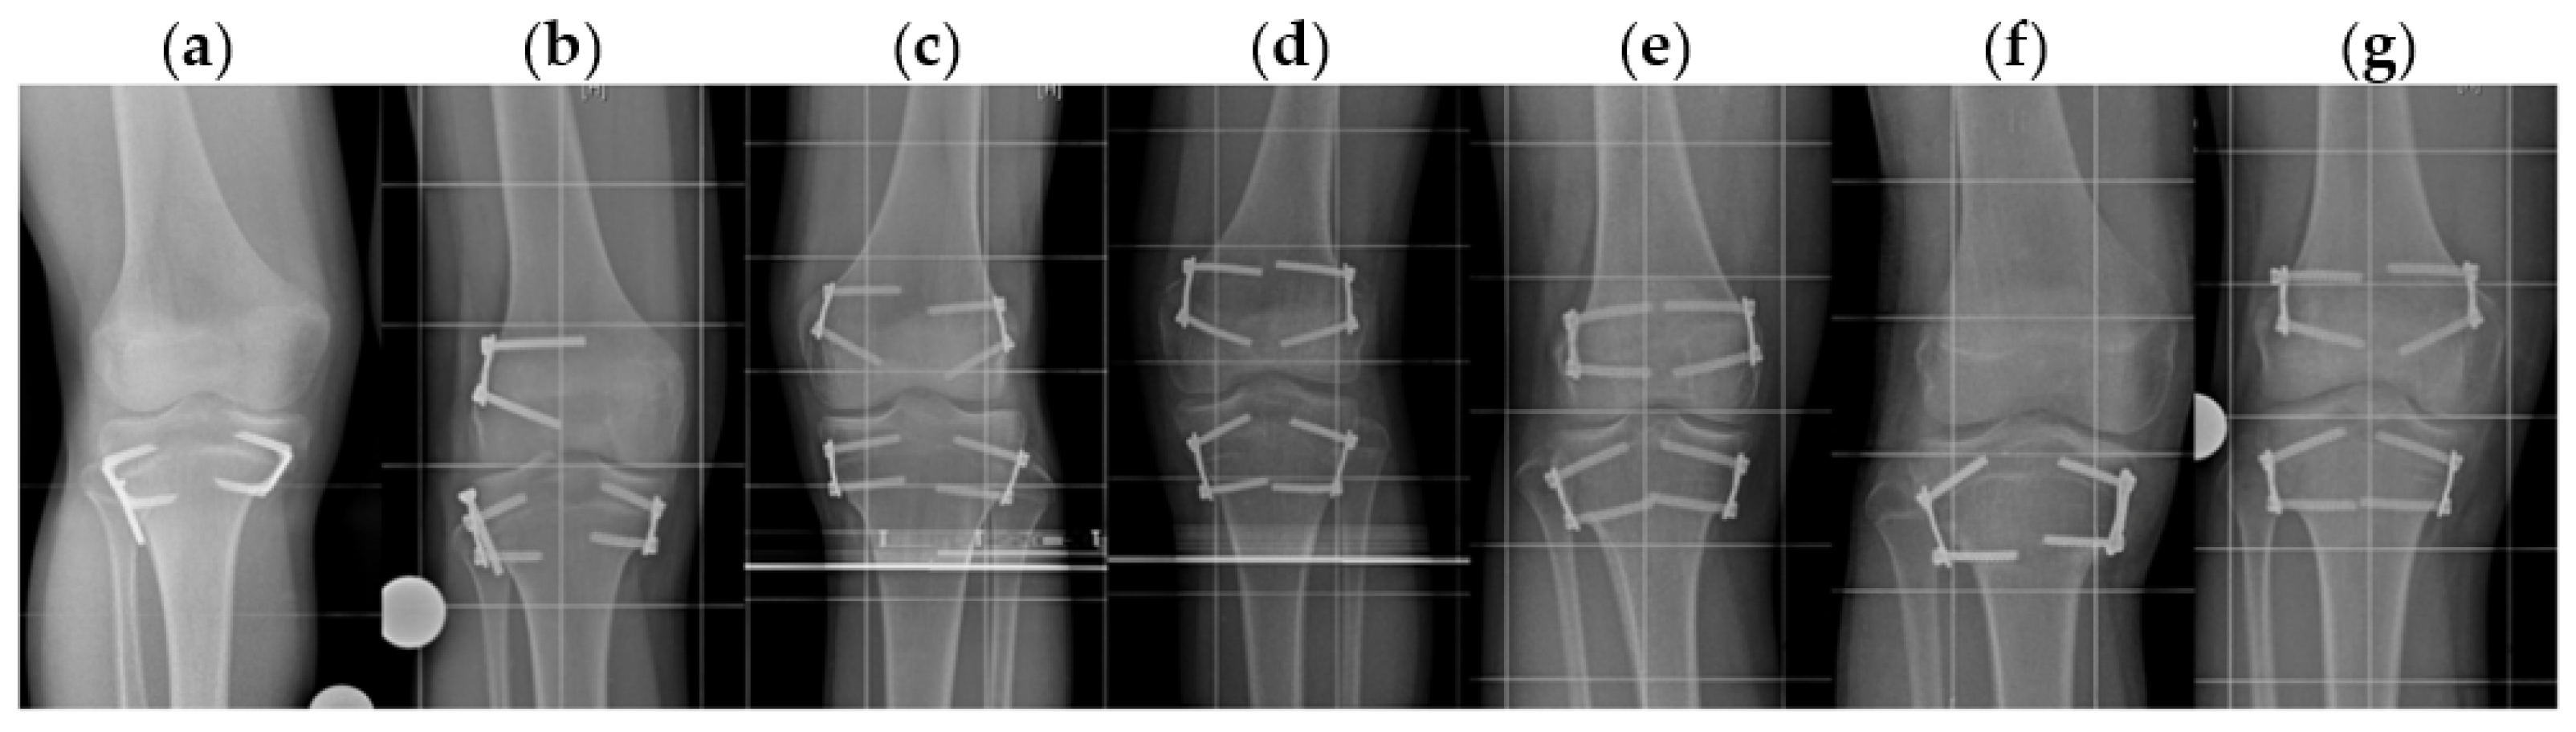

2.2. Indication, Operative Technique, and Applied Implants

2.3. Implants Applied for Epiphysiodesis

2.5. Radiographic Analysis